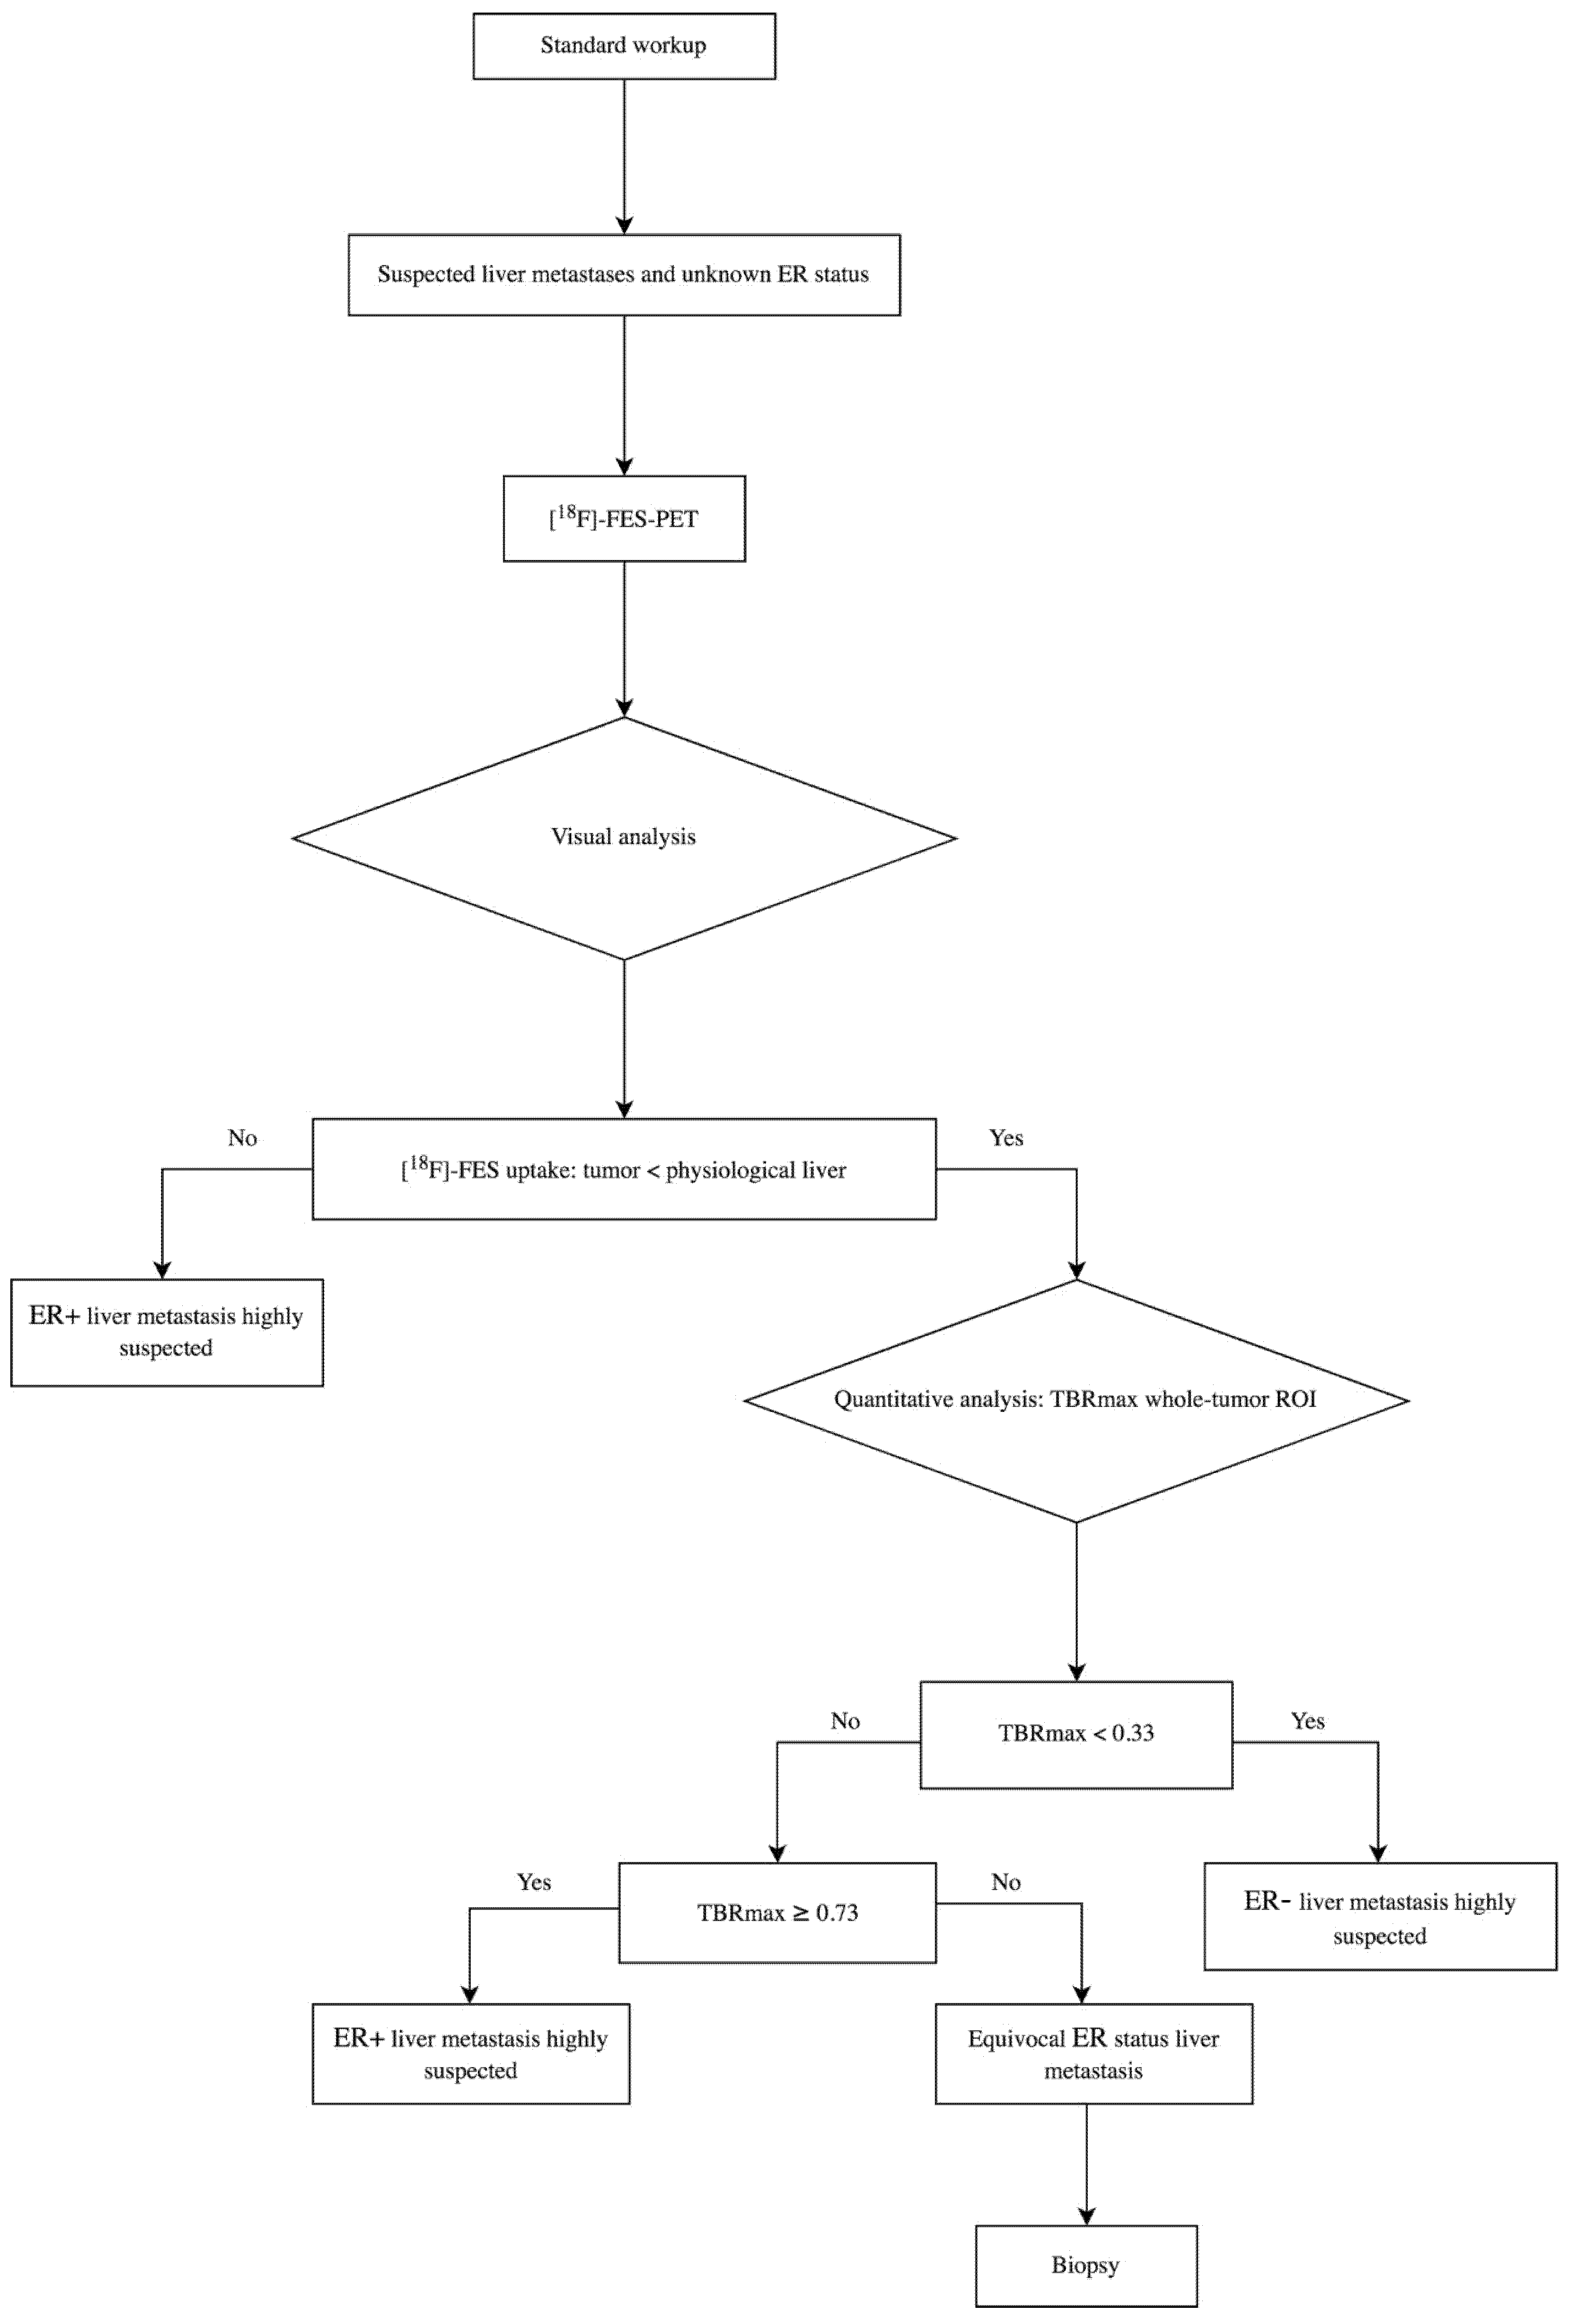

3.6. Lower and Upper Cut-Off Values

| TBRmax | whole-tumor | <0.33 | ≥0.69 | 75 | 100 | 22 |

| TBRmax | whole-tumor | <0.33 | ≥0.73 | 75 | 100 | 30 |